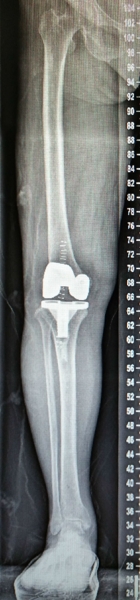

罗圈腿在医学上称为“膝内翻畸形”,又叫“O型腿”,能引起膝内翻畸形的疾病包括:维生素D缺乏性佝偻病、膝关节内侧半月板损伤退变、骨关节炎、创伤性关节炎等。膝内翻畸形的患者不仅走路不美观,更重要的是膝内翻畸形改变了下肢原有正常的受力状态,使膝关节内侧间隙的负重明显增加,久而久之出现相应部位的软骨面磨损、老化,最终发展演变为骨关节炎,出现日益严重的关节疼痛。在这一病理过程的早期,在软骨完好,关节间隙没有狭窄时,如果及早行截骨矫形术(如胫骨高位截骨术HTO)纠正畸形,则可从一定程度上延缓骨关节炎的发生,但如果已出现关节间隙的明显狭窄且疼痛严重,则需要行人工关节置换术(TKA或UKA)方能彻底地获得症状改善。